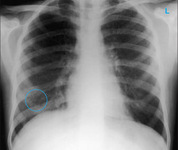

Chest x-ray showing left hilar carcinoma (arrow)

From: E. Dick, Student BMJ. 2000;8:358-360